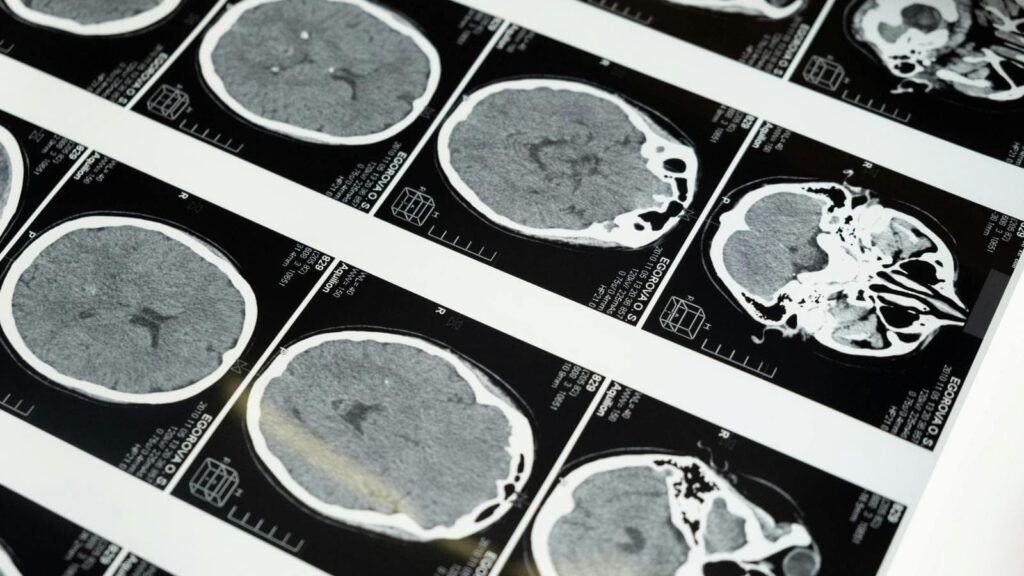

Many people label anxiety as a sentiment or a feeling. However, it is more than that. The amygdala, which is responsible for driving the brain’s threat response system is what actually prods the anxiety. The amygdala signals the hypothalamus to release the stress hormones named cortisol and adrenaline following a trigger of fight or flight response in counteracting the proposed threat perceived by the body. This sets off a series of physiological reactions, including elevated heart rate, irregular or rapid breathing, tense muscles, dilation of the pupils, perspiration, and increased awareness of the surrounding.